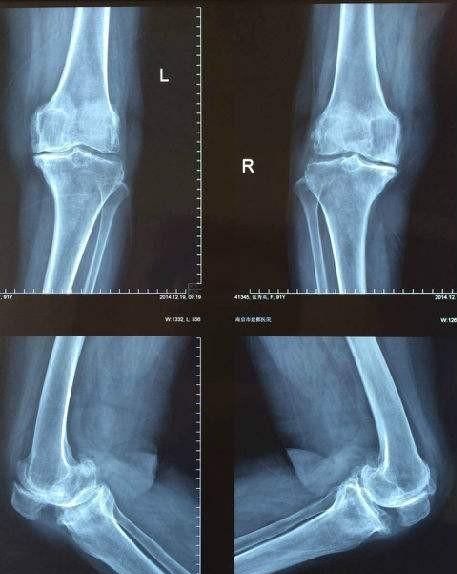

大腿骨里有骨刺,这个定位不准确。如果从医学术语上讲有两种情况,第一种是在骨干的地方有骨刺,我考虑很大程度上是骨软骨瘤。第二种是在大腿骨的末端,你或许指的是膝关节部位有骨刺,这只是一个骨质增生。

第二种情况,骨关节炎。骨关节炎是人关节退行性改变的一种。这是一个骨质增生的表现。如果你膝关节出现疼痛,你可以对症口服止痛药,服用一些治疗膝关节炎的药物。同时注意保健和理疗。如果没有症状的话,那也不需要处理。只需要平时保护膝关节就可以了。